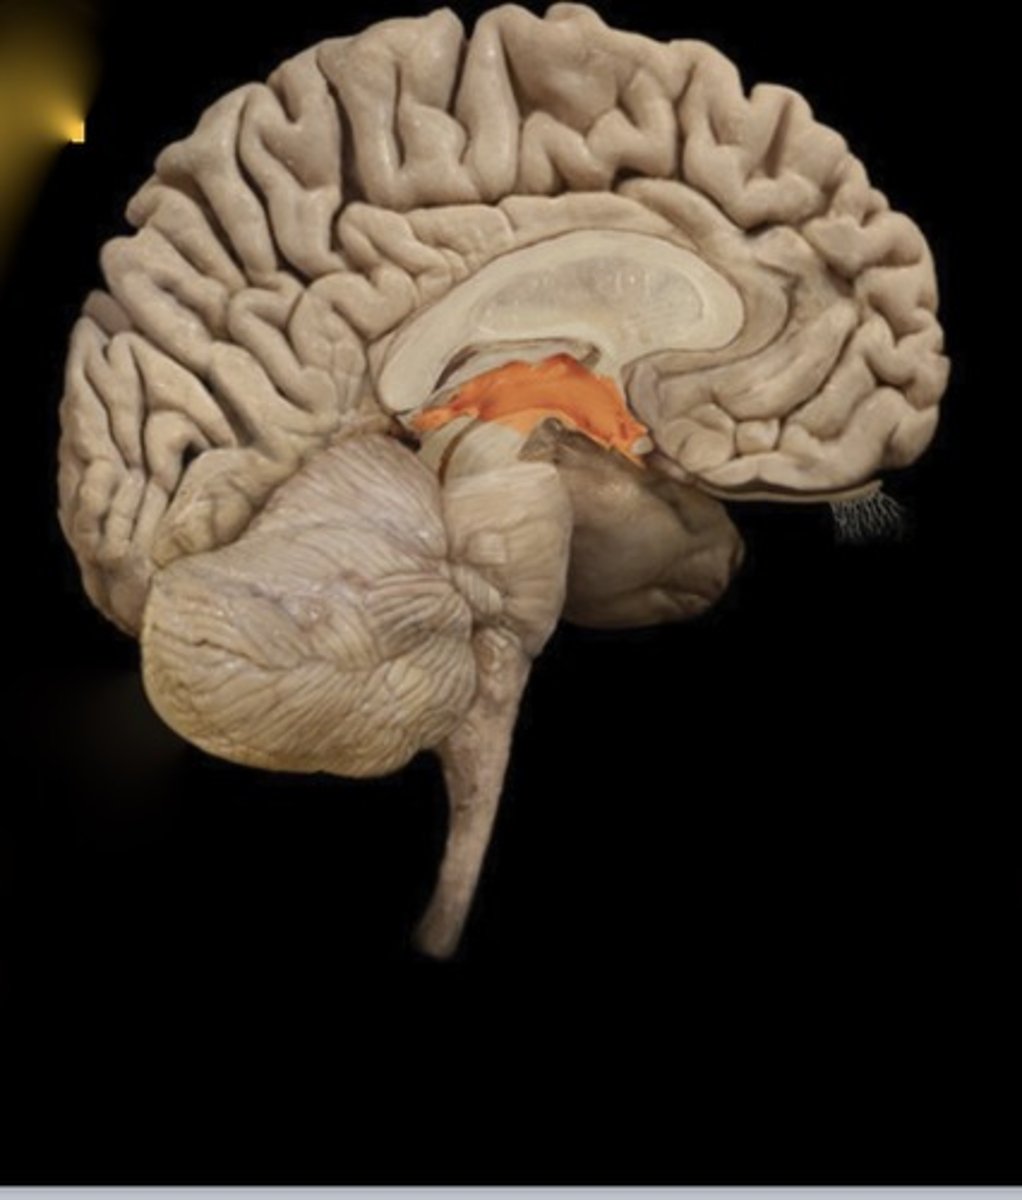

Corpus Callosum

Name this structure

Thalamus

Name this structure

Hypothalamus

Name this structure

Pineal gland

Name this structure

Mamillary Body

Name this structure

Pituitary gland

Name this structure

Third Ventricle

Name this structure

Fourth Ventricle

Name this structure